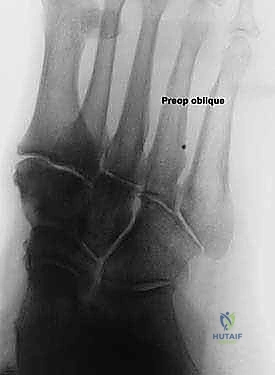

* الأشعة السينية (X-rays) مع تحمل الوزن: ضرورية لتقييم درجة انهيار القوس وزوايا العظام (مثل زاوية تالونافيكولار Meary's Angle).